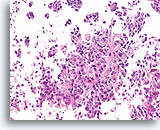

Lobulair carcinoom, Borst FNA, celblok.

Lobulaire carcinoomcellen lijken in het stromaweefsel te zijn ingebed, zodat de indruk wordt gewekt van hypercellulariteit. Dit kan de reden zijn waarom cytologische preparaten van een lobulair carcinoom vaak weinig maligne cellen tonen.

20X

Lobulair carcinoom, Borst FNA, celblok.

Lobulaire carcinoomcellen lijken in het stromaweefsel te zijn ingebed, zodat de indruk wordt gewekt van hypercellulariteit. Dit kan de reden zijn waarom cytologische preparaten van een lobulair carcinoom vaak weinig maligne cellen tonen.

20X

Lobulair carcinoom, Borst FNA, celblok.

Een enkele rij minimaal atypische spaarzame cellen die op en in de stromale fragmenten vastzitten, kan worden waargenomen. Let op de kenmerkende targetoïde intracytoplasmische vacuolen van lobulaire neoplasie.

40X

Lobulair carcinoom, Borst FNA, celblok.

Een enkele rij minimaal atypische spaarzame cellen die op en in de stromale fragmenten vastzitten, kan worden waargenomen. Let op de kenmerkende targetoïde intracytoplasmische vacuolen van lobulaire neoplasie.

40X